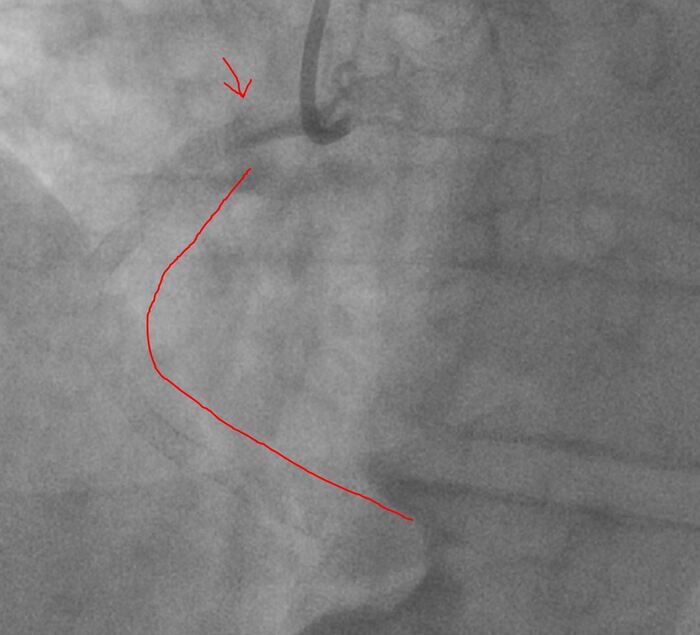

Сразу после этого начато лечение ПКА - ангиопластика (расширение суженных участков) с последующим стентированием. Однако, при проведении стента к пораженному участку (после ангиопластики) возникло осложнение - спиральная протяженная диссекция (расслоение правой артерии в проксимальном сегменте), вероятно, катетер-индуцированная (ятрогенная).

Желтыми стрелками показана зона расслоения сосуда